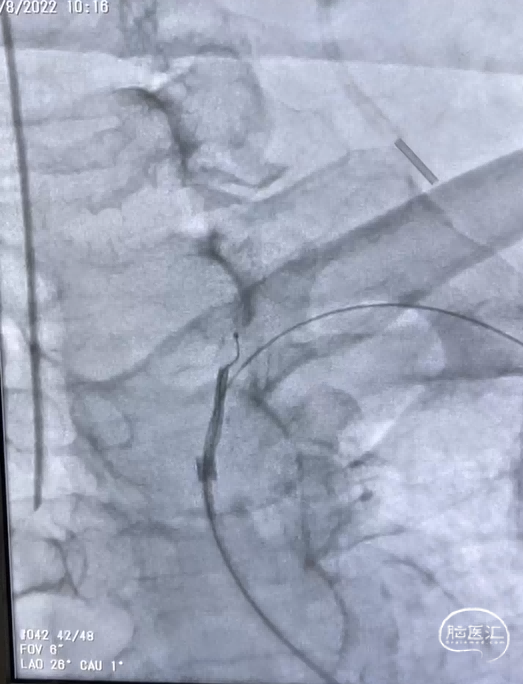

图7. 尝试开通左侧椎动脉

综合术前辅助检查,(Core+pen)/Core=3.58;Pen>15ml;Core<70ml(图3);发病时间小于24小时,存在取栓指征,但是当地医院手术经验告诉我们左侧椎动脉慢性闭塞,且开通异常困难,常规手术方案很难成行,术前制定合理且可行的手术方案至关重要。方案1:仍采用左侧椎动脉+基底动脉取栓的正向开通方案,可能会继续浪费大量时间,甚至最后以失败告终。方案2:采用右侧椎动脉入路,由于右侧椎动脉V4段发育不良,当地医院已尝试过超选,证实无法通过V4段至基底动脉建立取栓通路。方案3:既往有文献报道开颅椎动脉直视下穿刺取栓,虽然方案可行,但我院无类似手术经验,贸然尝试风险难以把控。方案4:回顾当地医院取栓影像资料,发现双侧颈内动脉后交通呈胚胎型,是否可能通过后交通跨循环逆向超选至基底动脉取栓。患者平卧DSA床,全麻插管成功后,用碘伏常规消毒手术区皮肤,铺无菌巾单。取双侧股动脉为穿刺点,于14时00分seldinger法穿刺成功后分别置入8F穿刺鞘和5F 短鞘。行全脑血管造影显示左侧椎动脉起始部闭塞,颈升动脉通过肌支代偿V2及以远的椎动脉血流,右侧椎动脉V4段发育不良,单纯供应右侧PICA,双侧后交通动脉胚胎型。(图9,图10)首先我们仍尝试传统入路进行超选左侧椎动脉,发现左侧椎动脉开口闭塞,斑块质地坚硬,微导丝微导管无法通过。短暂尝试无果后,迅速改为右侧椎动脉入路,发现将微导丝塑型成“J”型或成袢,均无法到达右侧椎动脉V4段,遂果断决定采用跨循环取栓方案。将5F VERT造影导管超选至左侧锁骨下动脉,进行正向血流监测。6F 90cm长鞘(cook)及5F 125cm Navien导管在泥鳅导丝带领下超选进入右侧颈内动脉岩骨段。随后将Rebar18微导管在Synchro2微导丝带领下超选至大脑中动脉,并将Navien带领至右侧颈内动脉交通段。微导丝微导管回撤至颈内动脉,路图下Synchro2微导丝带领Rebar18逐步通过右侧后交通动脉,再在透视下经右侧大脑后动脉P1段盲超选至基底动脉下段。(图11-13)手推造影确认Rebar18微导管已突破血栓段,并在基底动脉真腔内。(图14)经Rebar18释放一枚solitaire FR支架(4mm×20mm)覆盖血栓段。SWIM技术负压下抽拉支架1次,抽拉过程中时刻注意系统张力,逐步回撤支架同时适度回撤Navien释放张力,以保证Navien贴近后交通开口而不向后交通动脉内继续深入。撤出支架后,Navien原位保持负压约30秒。(图15)造影复查见基底动脉及其分支再通,支架取出少量血栓(图18)。于14时45分达到远端血流mTICI3级,10分钟后复查造影显示血管通畅,于14时55分末次造影见远端血流维持mTICI3级。(图16,17)术中Dynamic CT未见明显术区出血(图19)。遂缝合穿刺点,结束手术。手术顺利,术中病人情况稳定。术末血压115/58mmHg,脉搏70次/分,呼吸12次/分,氧饱和度100%。术毕送重症监护室。图9. 双侧椎动脉造影:左侧椎动脉起始部闭塞,左侧颈升动脉肌支和右侧椎动脉通过脊髓支代偿V2及以远的椎动脉血流;右侧椎动脉V4段发育不良,单纯供应右侧PICA